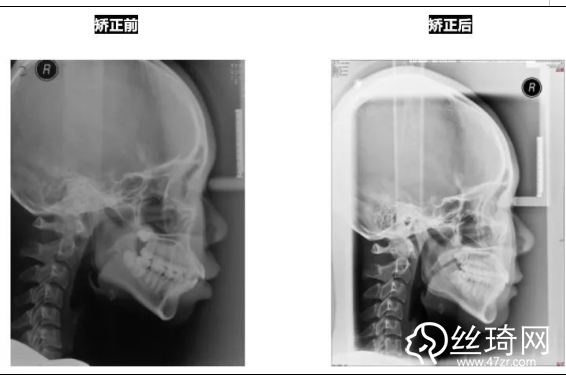

* 影像學(xué)檢查分析(以及調(diào)節(jié)前后影像對比):

全景片:

頭顱側(cè)位片:

前后頭影測量結(jié)果對比:

所以,正畸調(diào)節(jié)前齊全的資料收集和縝密的測量分析是優(yōu)質(zhì)調(diào)節(jié)方案的基礎(chǔ),大家了解了嗎?